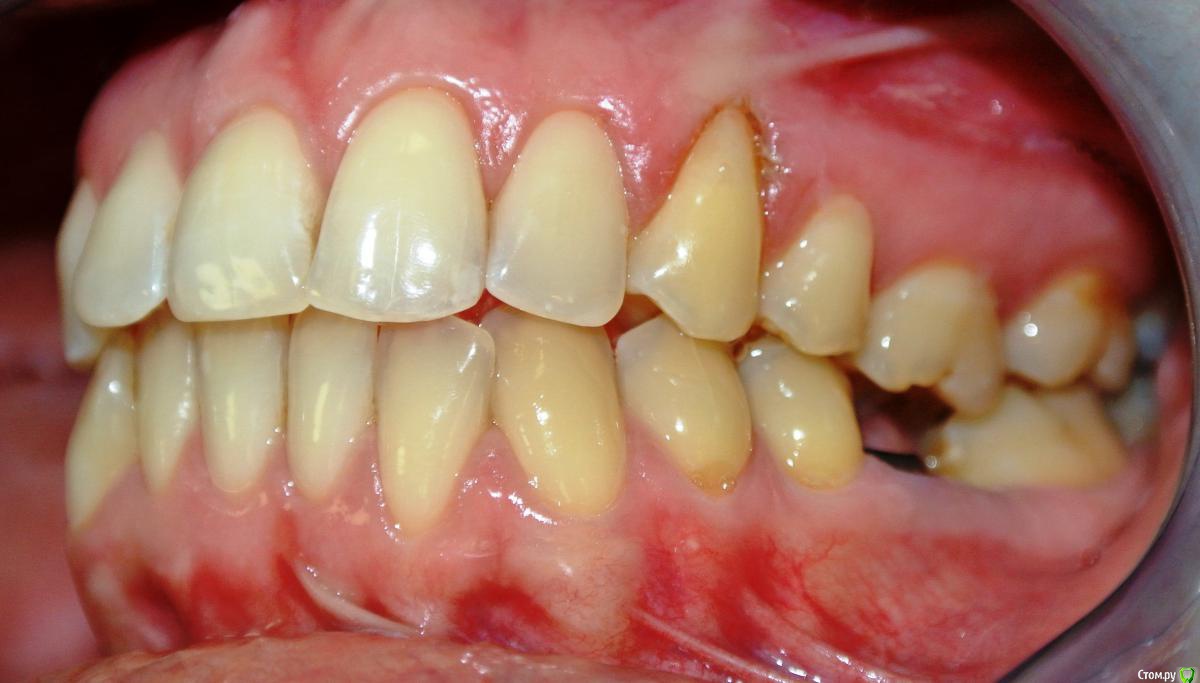

Dina_N Опубликовано 2 апреля, 2015 Поделиться Опубликовано 2 апреля, 2015 Пациентка Н., 30 лет. Жалоба на смещение средней линии верхнего зубного ряда. Из анамнеза: зуб 1.3. удален в возрасте 9 лет (ох уж эти удаляльщики). Как можно скорректировать положение средней линии? Ссылка на комментарий

Yana guapa Опубликовано 2 апреля, 2015 Поделиться Опубликовано 2 апреля, 2015 Хорошо бы фото с улыбкой в полный фас , т.к. средние линии лица, носа, губ, ВЧ и НЧ все между собой могут не совпадать. Судя по данным фото, смещение средней линии ВЧ присутствует, но в большей степени здесь играет роль уплощение ВЧ справа. Поэтому и расширять в данном месте нужно, устранять асимметрию ВЧ, с восстановлением дефекта з/р (имплантацией клыка) . Вся ВЧ сужена. Раскрывать под клык надо. Ссылка на комментарий

Skip Опубликовано 4 апреля, 2015 Поделиться Опубликовано 4 апреля, 2015 А я бы не стал здесь раскрывать пространство для клыка, а раскрыл бы место между премолярами для имплантата, а из 4-ки сделал бы клык. Догадайтесь, почему..?И ещё один маленький нюанс. Без кортикотомии (а возможно и остеотомии) там трудно будет осуществить всю эту механику, это ведь не подросток с заблокированным в кости клыком. 1 Ссылка на комментарий

Yana guapa Опубликовано 4 апреля, 2015 Поделиться Опубликовано 4 апреля, 2015 А я бы не стал здесь раскрывать пространство для клыка, а раскрыл бы место между премолярами для имплантата, а из 4-ки сделал бы клык. Догадайтесь, почему..? могу предположить, что если четверку оставить на месте, то дистализировать зубов меньше уже надо.(вперед толкать зубы итак уже некуда, не эстетично будет). и плюс четверка в кости сейчас хорошо находится. А если раскрывать в области клыка, то возможно будет провал в альвеолярной части . Ссылка на комментарий

Skip Опубликовано 4 апреля, 2015 Поделиться Опубликовано 4 апреля, 2015 и плюс четверка в кости сейчас хорошо находится. А если раскрывать в области клыка, то возможно будет провал в альвеолярной части . Всё верно, именно это я имел ввиду. Ссылка на комментарий